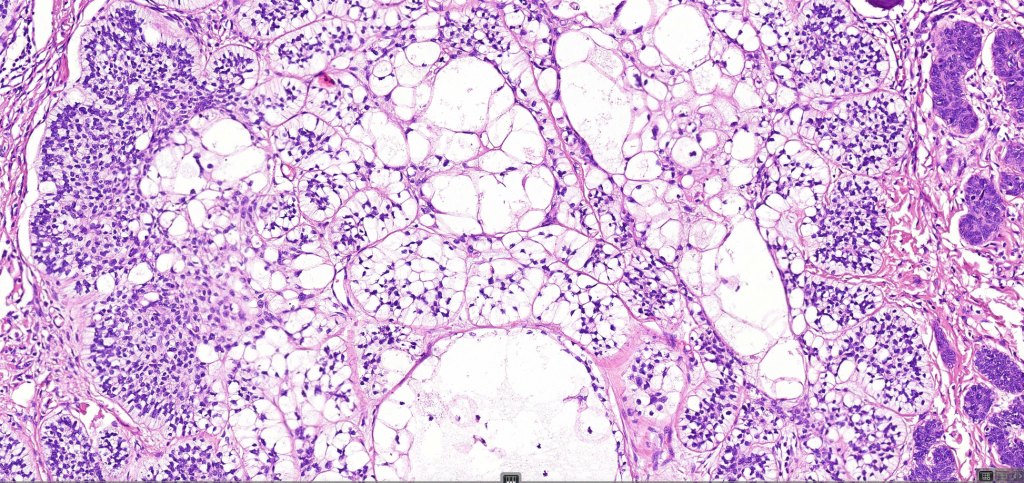

•Both epithelial & fibrous stromal components

•The tumor commonly arises from the epidermis

•The epithelial component is composed of uniform small, basophilic devoid of desmosomes

•Peripheral palisading

•Retraction artifact with stromal mucin

•Pseudoglandular appearance

•A wide variety of histological variants are possible including nodular, nodulocystic, ulcerative, superficial, micronodular, infiltrating/infiltrative, keratotic, basosquamous, pigmented, morpheaform, keloidal, clear-cell, signet-ring cell & granular cell variants, BCC with monster cells, BCC with metaplastic features, BCC with matricial differentiation, basomelanocytic tumor (see separate blog), BCC with thickened basement membrane, BCC with carcinoid-like nuclear palisading & these are illustrated below